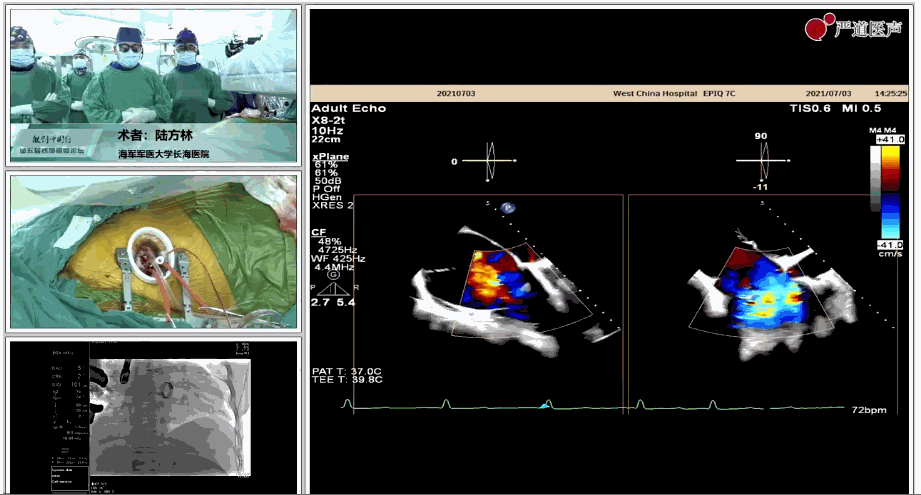

7月3日下午,海軍軍醫(yī)大學附屬上海長海醫(yī)院心血管外科徐志云、陸方林團隊在論壇中分享了經導管三尖瓣置換術(LuX-Valve®)的手術直播演示。線下會議由陶涼教授、潘文志教授、喬晨暉教授共同參與討論和臨床分享。

陸方林教授分享的是一例極重度三尖瓣返流的患者采用健世科技(LuX-Valve®)經導管三尖瓣置換系統(tǒng)進行的手術直播演示。此例患者為69歲女性,入院前17年行二尖瓣機械瓣置換術,術后長期服用華法林抗凝,既往“2型糖尿病”病史5年,“雙下肢水腫”3年。3個月前患者出現(xiàn)腹脹、雙下肢水腫,伴活動后暈厥,伴黃疽、皮膚濕癢、牙齦出血,癥狀持續(xù)加重,遂入院治療。入院后行心臟CT、心臟超聲檢查,提示:“三尖瓣關閉不全(極重度),二尖瓣置換術后,心功能III級”。徐志云、陸方林微創(chuàng)三尖瓣置換團隊對該患者的病情進行了充分的評估和討論。由于患者有開胸二尖瓣置換手術史,且病史時間長,同時存在相關合并癥,傳統(tǒng)外科手術風險極高(STS評分:8.315%),最終決定采用三尖瓣LuX-Valve®瓣膜系統(tǒng)對患者進行治療。

▲術中食道超聲顯示三尖瓣極重度返流